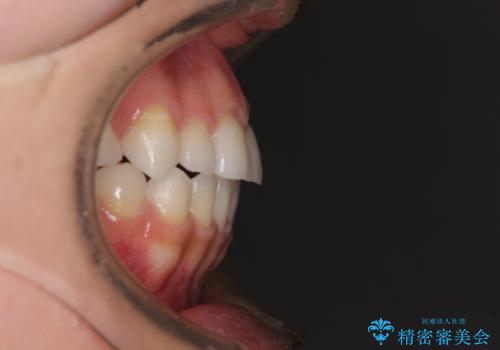

- 前歯のデコボコや八重歯、舌癖による開咬を気にして来院された患者様です。

目立たない装置を希望されたので、上顎が裏側装置のハーフリンガルを選択し、上顎小臼歯1本を抜歯して、補助装置を併用して矯正治療を行うこととしました。

補助装置を事前に使用したことで、あっという間に八重歯が改善し、ハーフリンガルにしては1年半もかからずに治療を終えることができました。